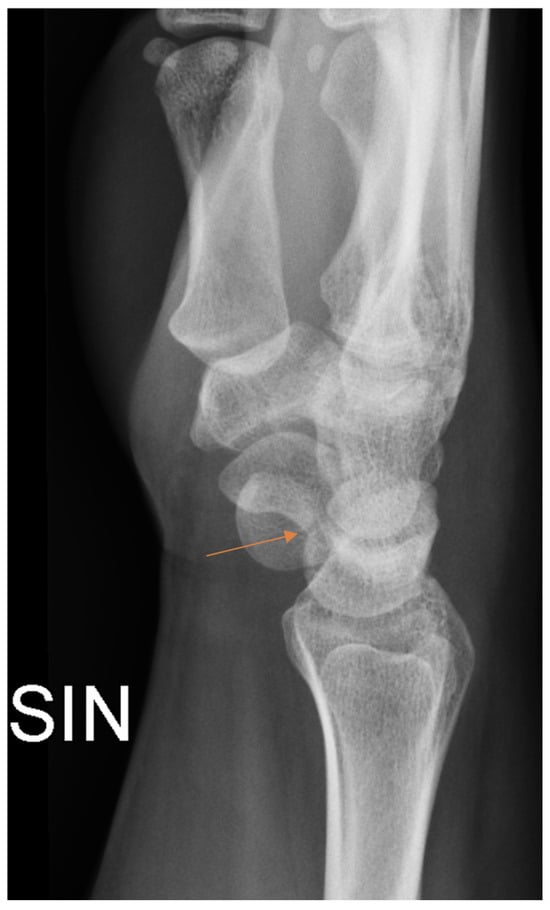

Figure 2.

Subtle radiographic finding in patient with scaphoid fracture (arrow) that was initially missed by the resident.